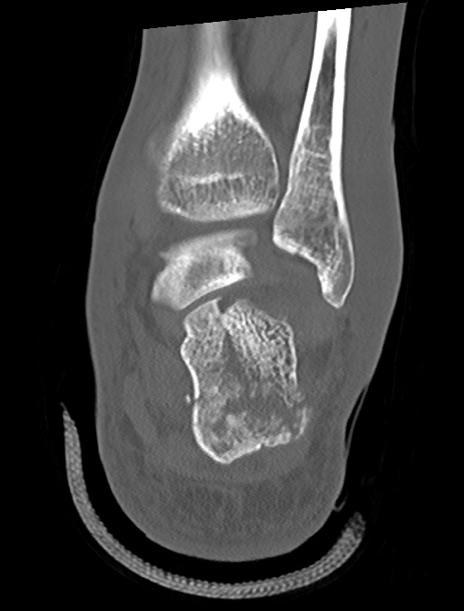

左足関節CT

矢状断像